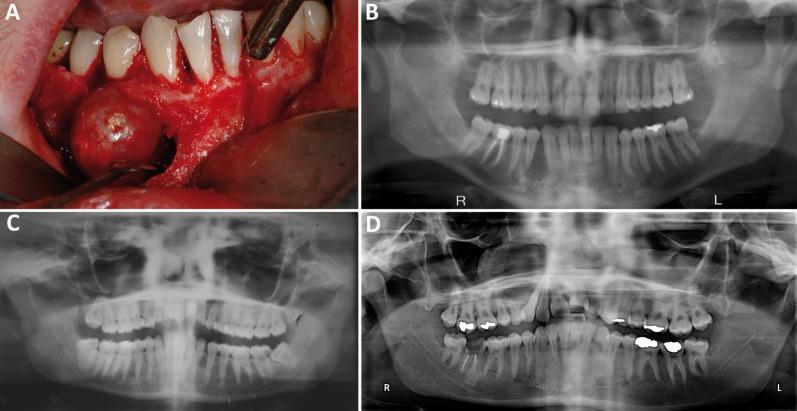

Fourteen AOT cases were reviewed, of which 12 were intraosseous and two were peripheral (gingiva). The cases came from eight females and six males with an age range of 11-30. Of the 12 intraosseous cases, nine were follicular (associated with impacted teeth), while three were extra-follicular (present between teeth). Six of the 12 cases were in the maxilla, and the other six were in the mandible. The two peripheral cases presented as nodules on the buccal gingiva of the anterior maxillary teeth. Radiographically, all 12 follicular and extra-follicular cases were unilocular radiolucencies; of those, only one had specks of radiopacity. Histologically, all specimens were similar in morphology, demonstrating a varied degree of duct-like structures, epithelial spheres, spindle-shaped epithelial cells, calcifications, and a thick capsule. The two peripheral cases had no capsule.

AOT usually affects patients under 20 years of age, with a female to male ratio close to 2:1. Presentation in the anterior maxilla is almost twice as common as in the anterior mandible. Radiographically, AOT presents as a unilocular radiolucency more commonly associated with impacted teeth, simulating a dentigerous cyst. We present 14 new cases of AOT (nine follicular, three extra-follicular, and two peripheral) with discussions of their clinical, radiographic, and histological features. Adenomatoid, odontogenic, tumor.